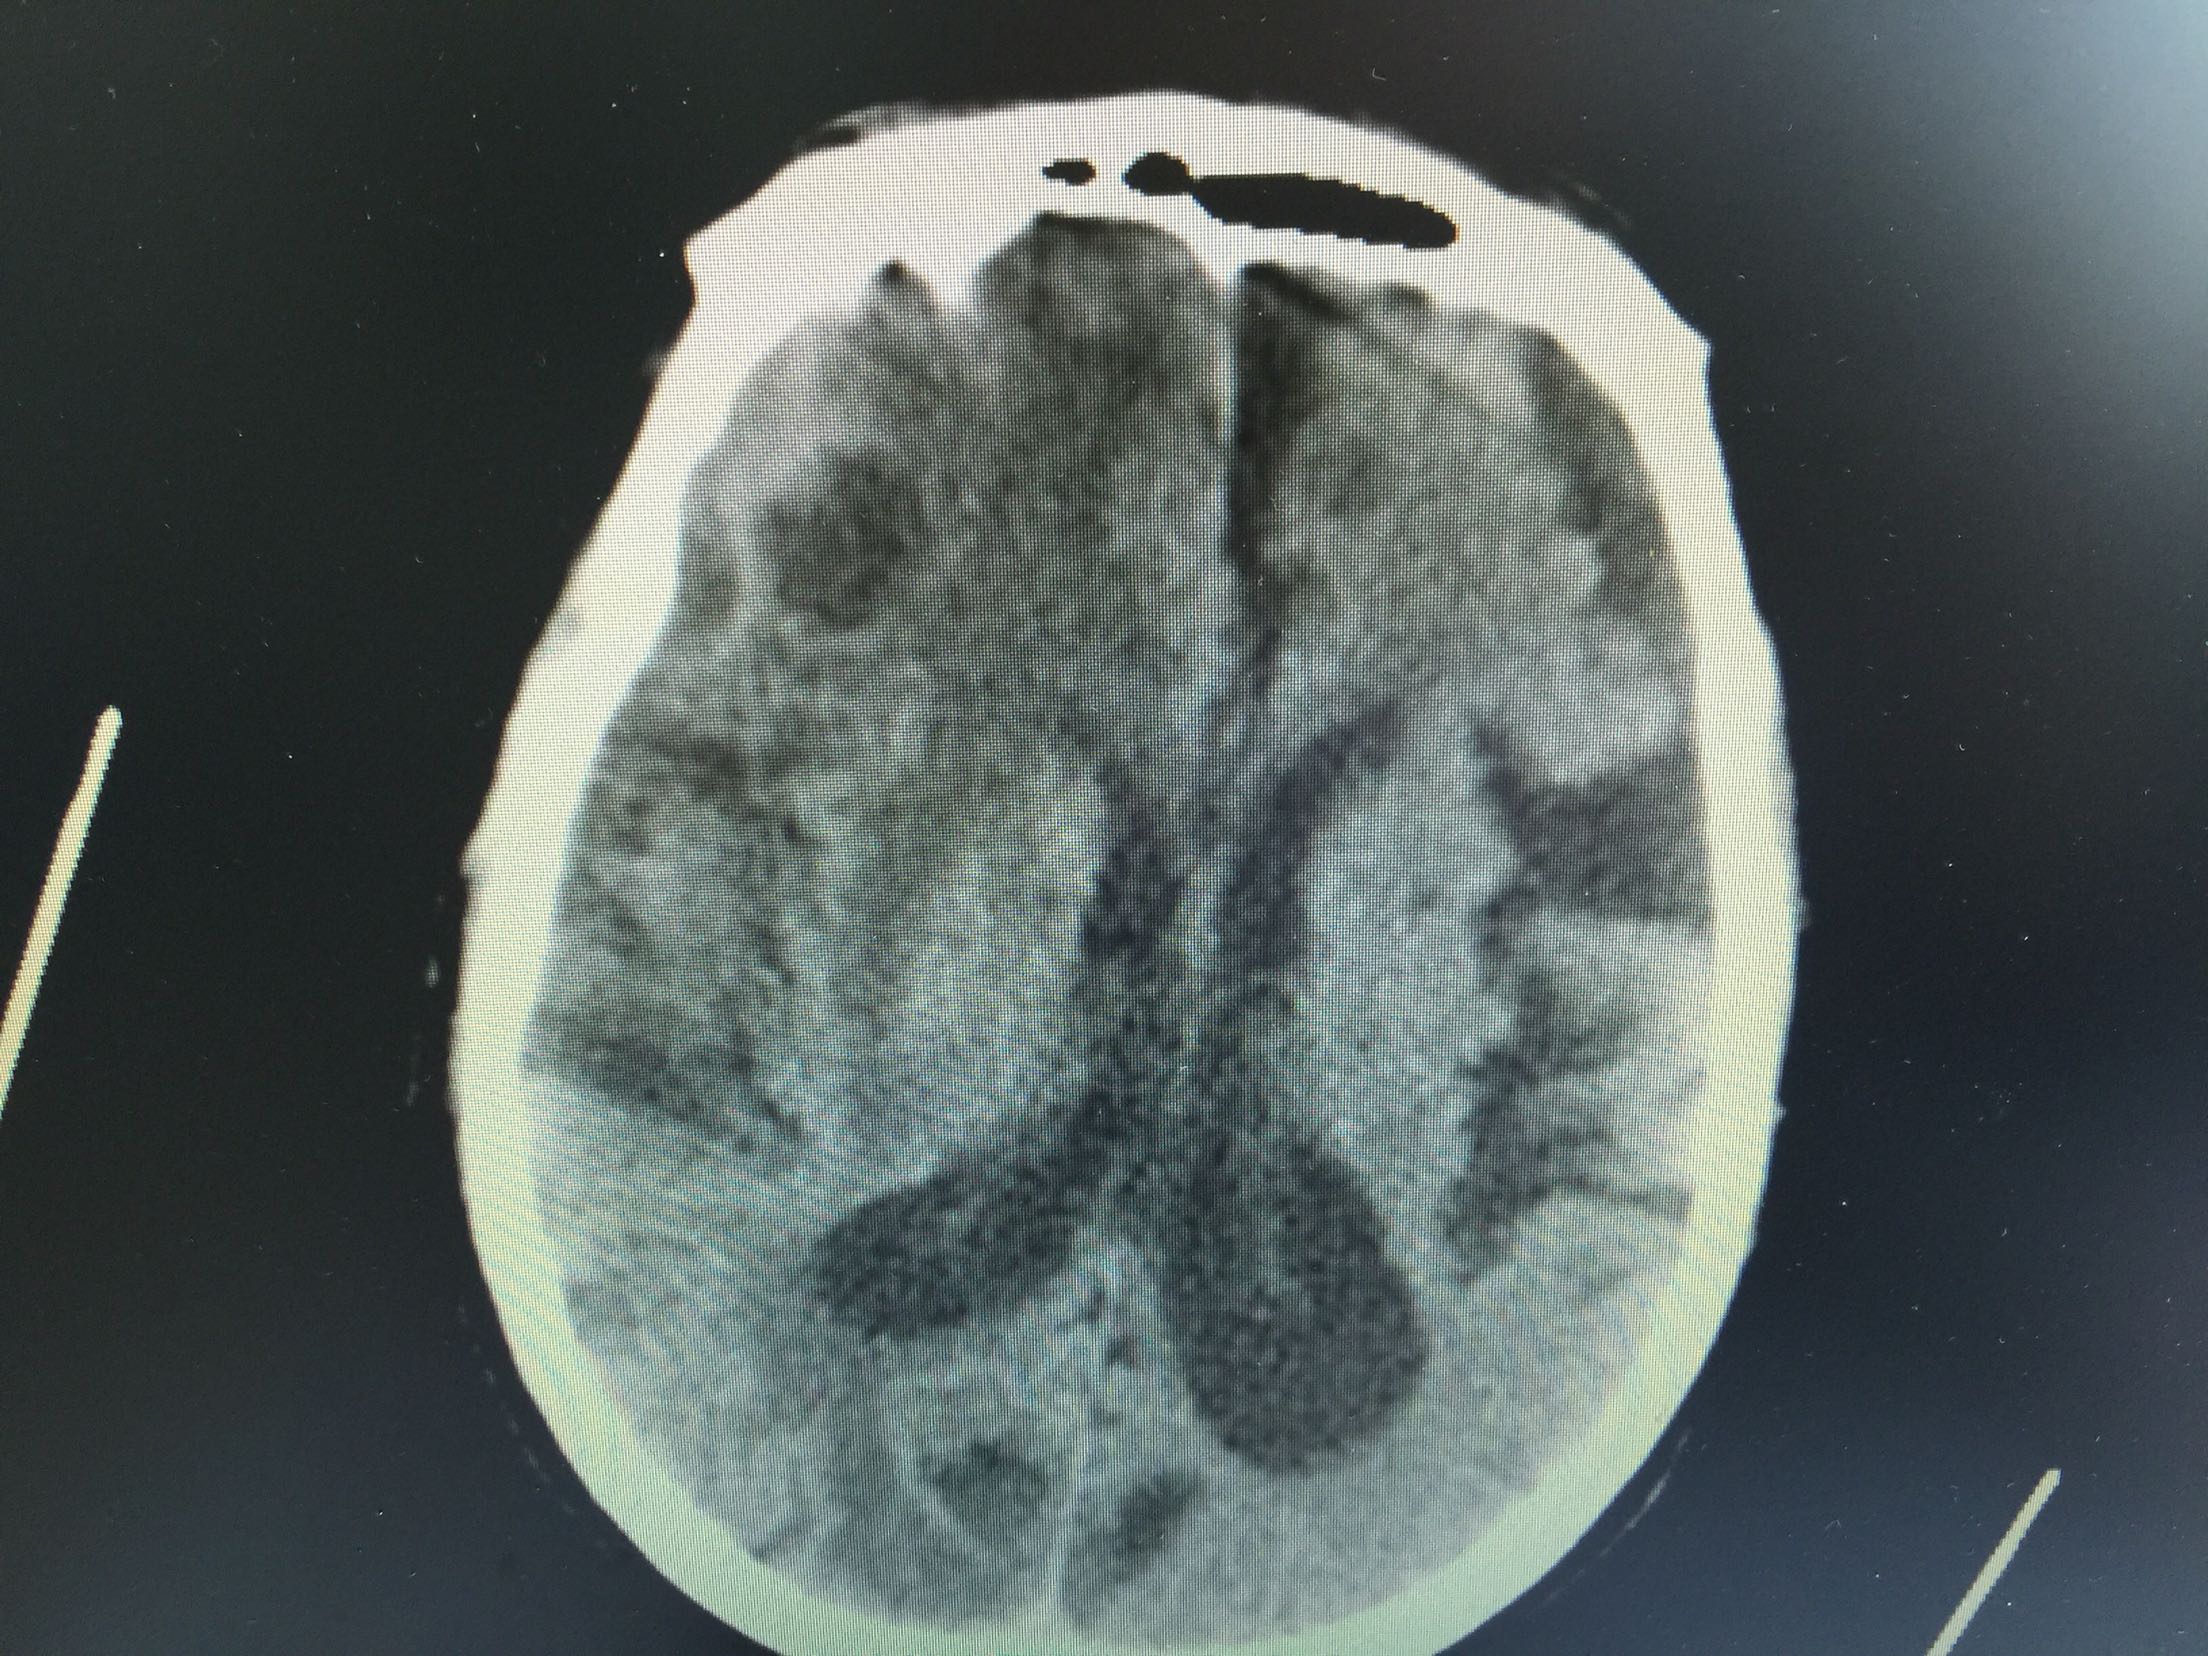

肺癌脑转移1例。

女,81岁,以“意识障碍1天”入院。

查体:浅昏迷,双眼向左侧凝视,双瞳孔等大正圆,直径3.0mm,对光反射灵敏,四肢不自主运动,肌张力正常,腱反射卄,Babinski征R-L-,脑膜刺激征阴性。

1.肺癌脑转移。 治疗:营养神经、脱水、抗感染、化痰、维持离子平衡治疗。